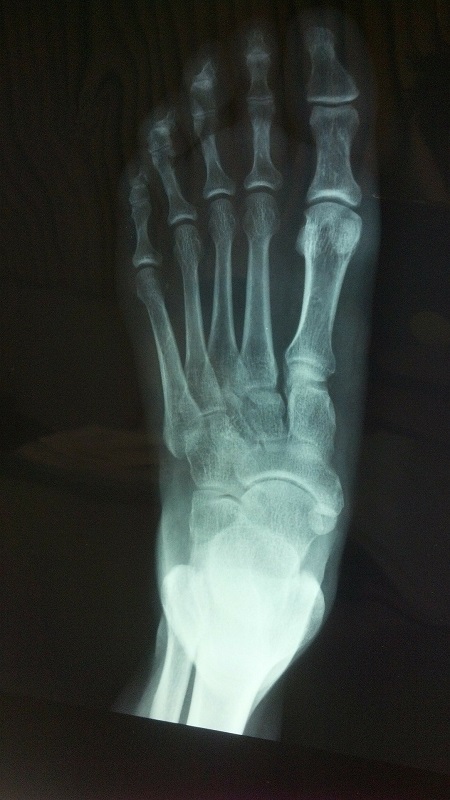

The foot is a complex structure consisting of several small bones, muscles, tendons, and other soft tissues responsible for bearing your weight and helping you navigate the world around …

Foot and ankle injuries are unfortunately very common. These types of injuries often occur when the ligaments that support the foot or ankle stretch beyond their limits and tear. …